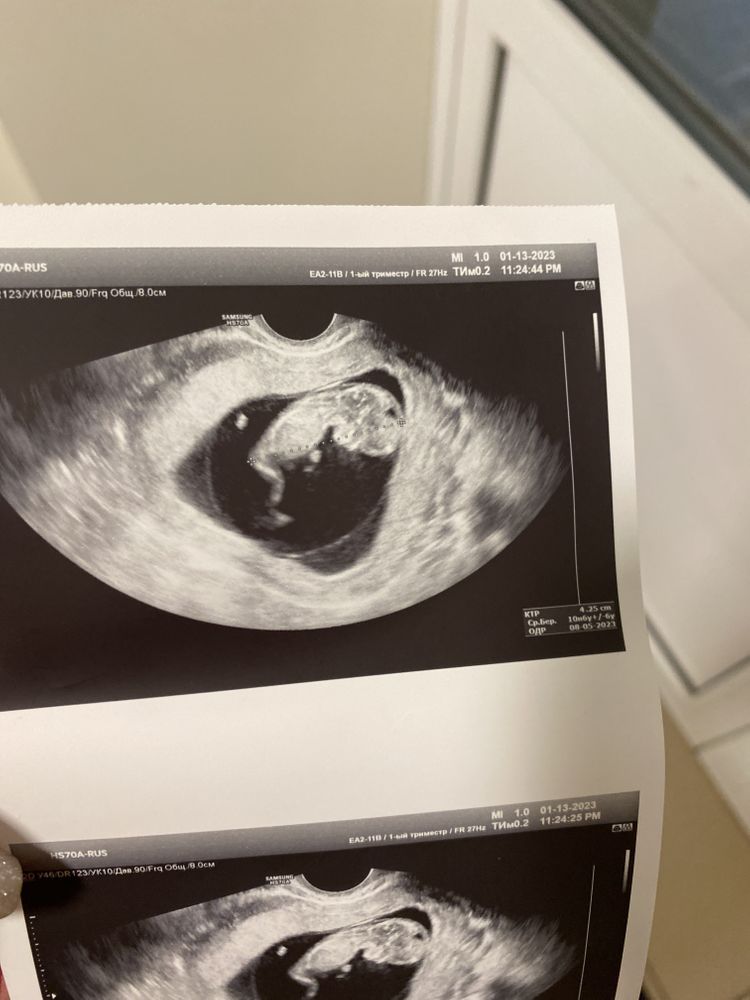

Темное пятно на голове

Кусок мозга. Если УЗИст не обратил внимания, значит всё хорошо. После так картинка получилась

УЗИ это отражение волн и под каждым углом отражает по разному. Пойдете в другой раз и поставят по другому и не будет пятна. Если бы в голове была такая дыра,то даже слепой УЗИст бы заметил.

Может аппарат так словил) врач если ничего не сказал, то значит все в порядке должно быть Спросили бы сразу у узиста

sequi, не переживайте! Сходите ещё раз на узи через пару неделек, попросите посмотреть этот момент